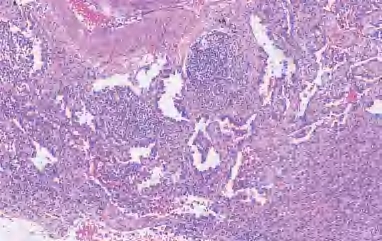

【镜下形态】MIA内浸润性腺癌成分是指腺泡型、乳头型、实体型和微乳头型腺癌,以及较少见的胶样、肠型、胎儿型和浸润性黏液性腺癌;或肿瘤细胞成分浸润至有肌纤维母细胞反应的肺间质,其中以腺泡型和乳头型腺癌最为常见(图2-3)。如血管、淋巴管、胸膜、肺泡内肿瘤细胞存在坏死和STAS等,则不能诊断为MIA,应诊断为浸润性腺癌。如果有多个浸润灶,浸润区在多个玻片上,浸润大小难以测量,可采用浸润性病灶的百分比之和×肿瘤的最大径,如数值≤0.5 cm,则诊断为MIA。

图2-3 MIA